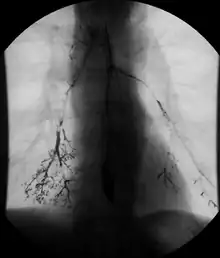

Normal barium swallow fluoroscopic image, showing the ingested barium sulfate being induced down the oesophagus by peristalsis. | |